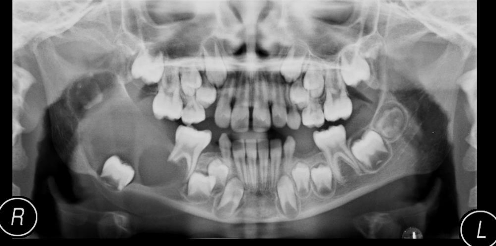

See image